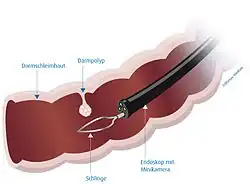

Pedunculated polyps can be removed by snare polypectomy. When the polyp is identified, a polypectomy snare is passed over the polyp and around the stalk of the polyp. The loop of the snare is then tightened to grip the polyp stalk, and the polyp is pulled away from the wall of the colon. An electric current is then passed through the snare loop to cut through the polyp stalk, providing electrocautery at the same time. The polyp can then be retrieved using the snare or an endoscopy basket, and removed by withdrawing the colonoscope.